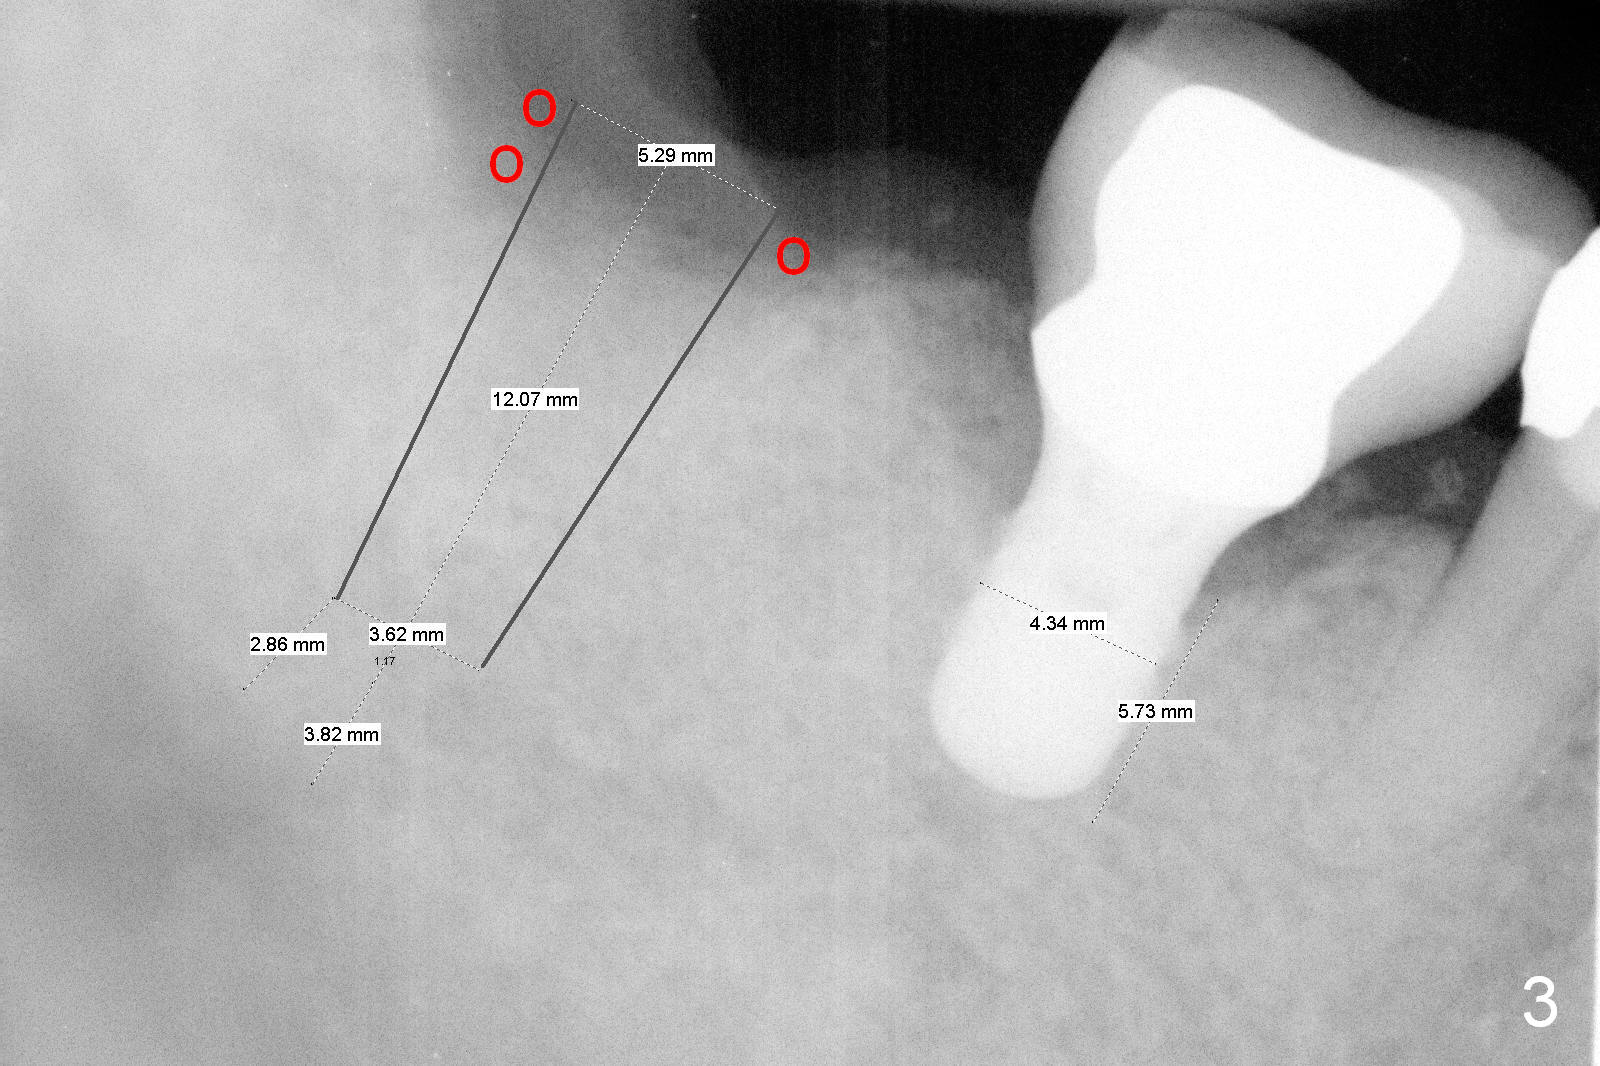

Fig.3 is a design to place a 5.3x12 bone level implant in the middle of the healing socket. The drawbacks are two folded. First the implant is placed too distally. Second, the implant is close to the underlying nerve.